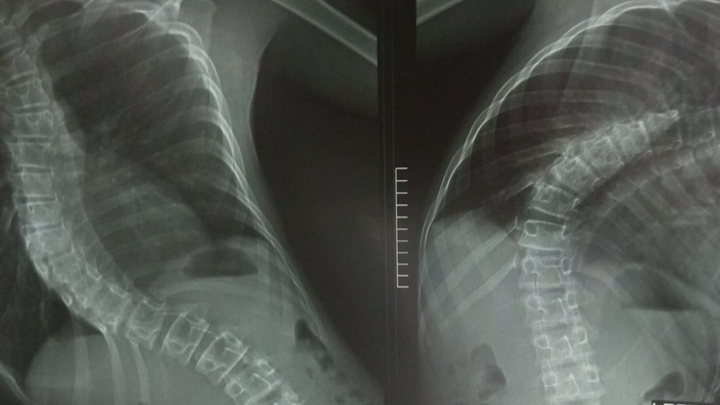

He has been diagnosed with thoracic dextroscoliosis, a severe spinal condition causing a significant curve in his spine. Over time, this has worsened, leading to pain, discomfort, and difficulties with movement. His recent MRI scan confirms that while his spinal cord remains intact, his scoliosis is progressing and requires medical intervention.

At just 14 years old, he is at a critical stage where treatment can significantly improve his quality of life. Without proper medical care, his condition could lead to more severe complications, including breathing difficulties and long-term mobility challenges.